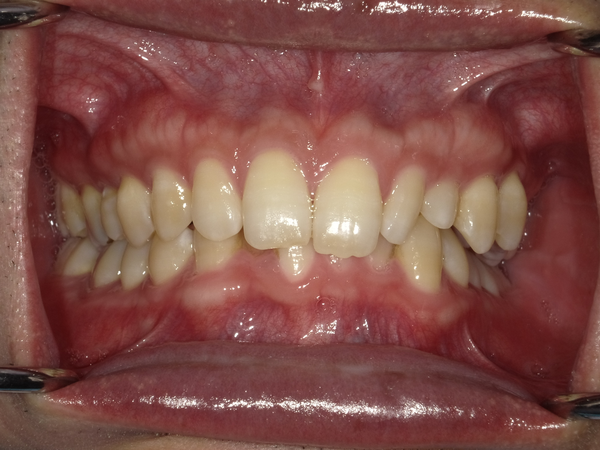

☆before→after☆◯ご相談内容:歯の叢生◯矯正の種類:マウスピース型矯正「インビザラインGO」◯治療期間:10週間◯治療費用:44万円(税込)